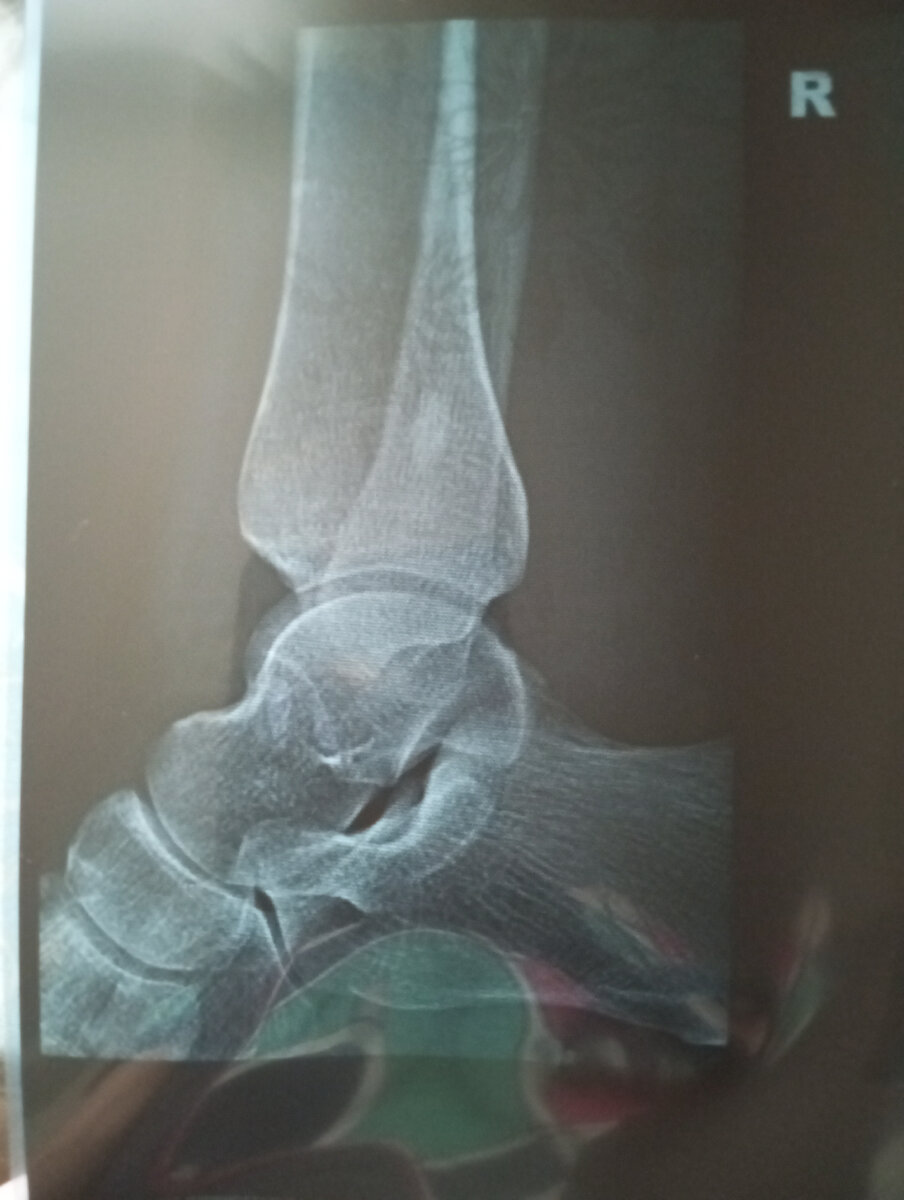

Что у меня стряслось с ногой? Рентген показал какую-то ерунду на кости. Нет ни трещины, ни ушиба, ни вывиха. Есть узелковая опухоль. В интернете порыла информацию, что медикаментозно она не лечится, то есть операция. Буду ждать теперь вердикт врача.